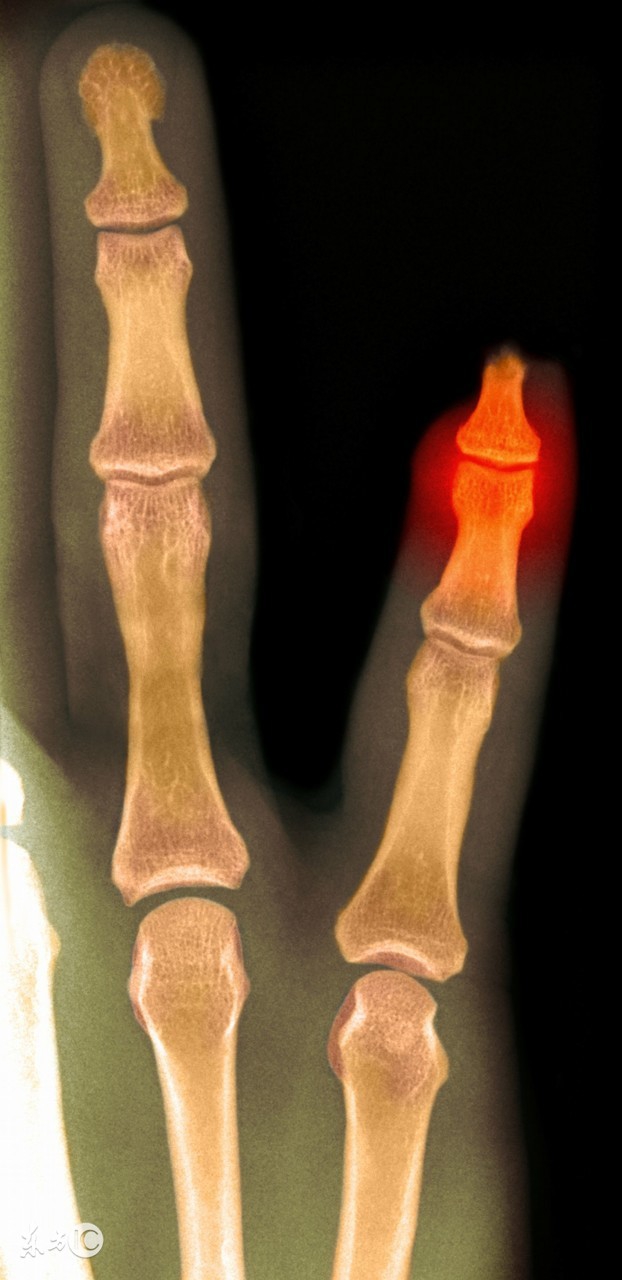

现场答疑阶段,一位妈妈提问说:“我家孩子在3岁的时候,跑步摔倒,右手小拇指骨折了,也在医生的指导下打了石膏,康复之后发现右手小拇指跟左手小拇指长短不一样,请问专家,孩子小拇指没法继续长了怎么办?”

北京新世纪儿童医院小儿外科副主任医师曾向红医生说,“儿童骨折后只要对位对线良好,或通过手法复位后达至对位对线良好,即可通过妥善局部固定治疗,一般愈合较快,塑形能力较强。如果骨折断端有压缩的话可使长骨缩短,或者伤到长骨骨姤如骨骺撕脱骨折、关节内骨折等有可能影响到日后骨的生长,而与对侧手指相比较会出现骨的短缩,只要不影响手指的屈伸功能,没有成角畸形,一般不需要治疗。如果外伤当时骨断端对位对线不好,即使手法复位正骨后稳定性差,愈合后可能出现成角畸形及功能障碍,则需要行手术用克氏针或小钢板内固定,以保持手指在一条直线上愈合,不论是外固定还是内固定,对骨的短缩都是不能完全预防的。

由于手指是肢体的末端,容易因为创伤、水肿而出现血运障碍,小儿肢端组织娇嫩,故治疗原则上应不增加或少增加创伤的程度,以免出现末端血运障碍、坏死或遗留功能障碍反而得不偿失。也就是说能不手术就尽量不手术。

该宝宝的外伤愈合后手指短缩只要不影响手指活动,可以不需要治疗,日后的生长可能继续影响手指的长度,对生活和工作没有影响的话也是不需要治疗的;如果希望行手指的骨延长手术,技术要求很高、很精细,需等孩子成年后咨询手外科。由专科医生决定。